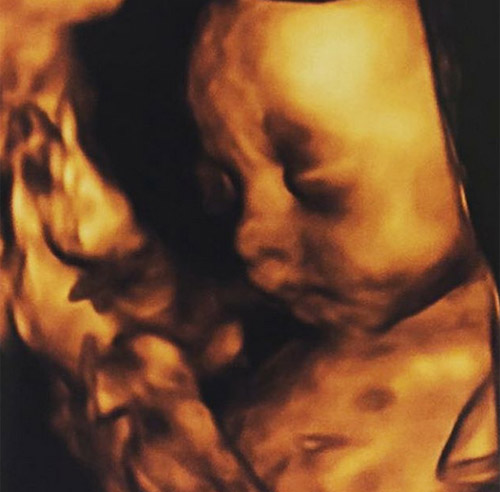

Hình ảnh siêu âm thai của em bé được Ernst Young chia sẻ trên mạng.